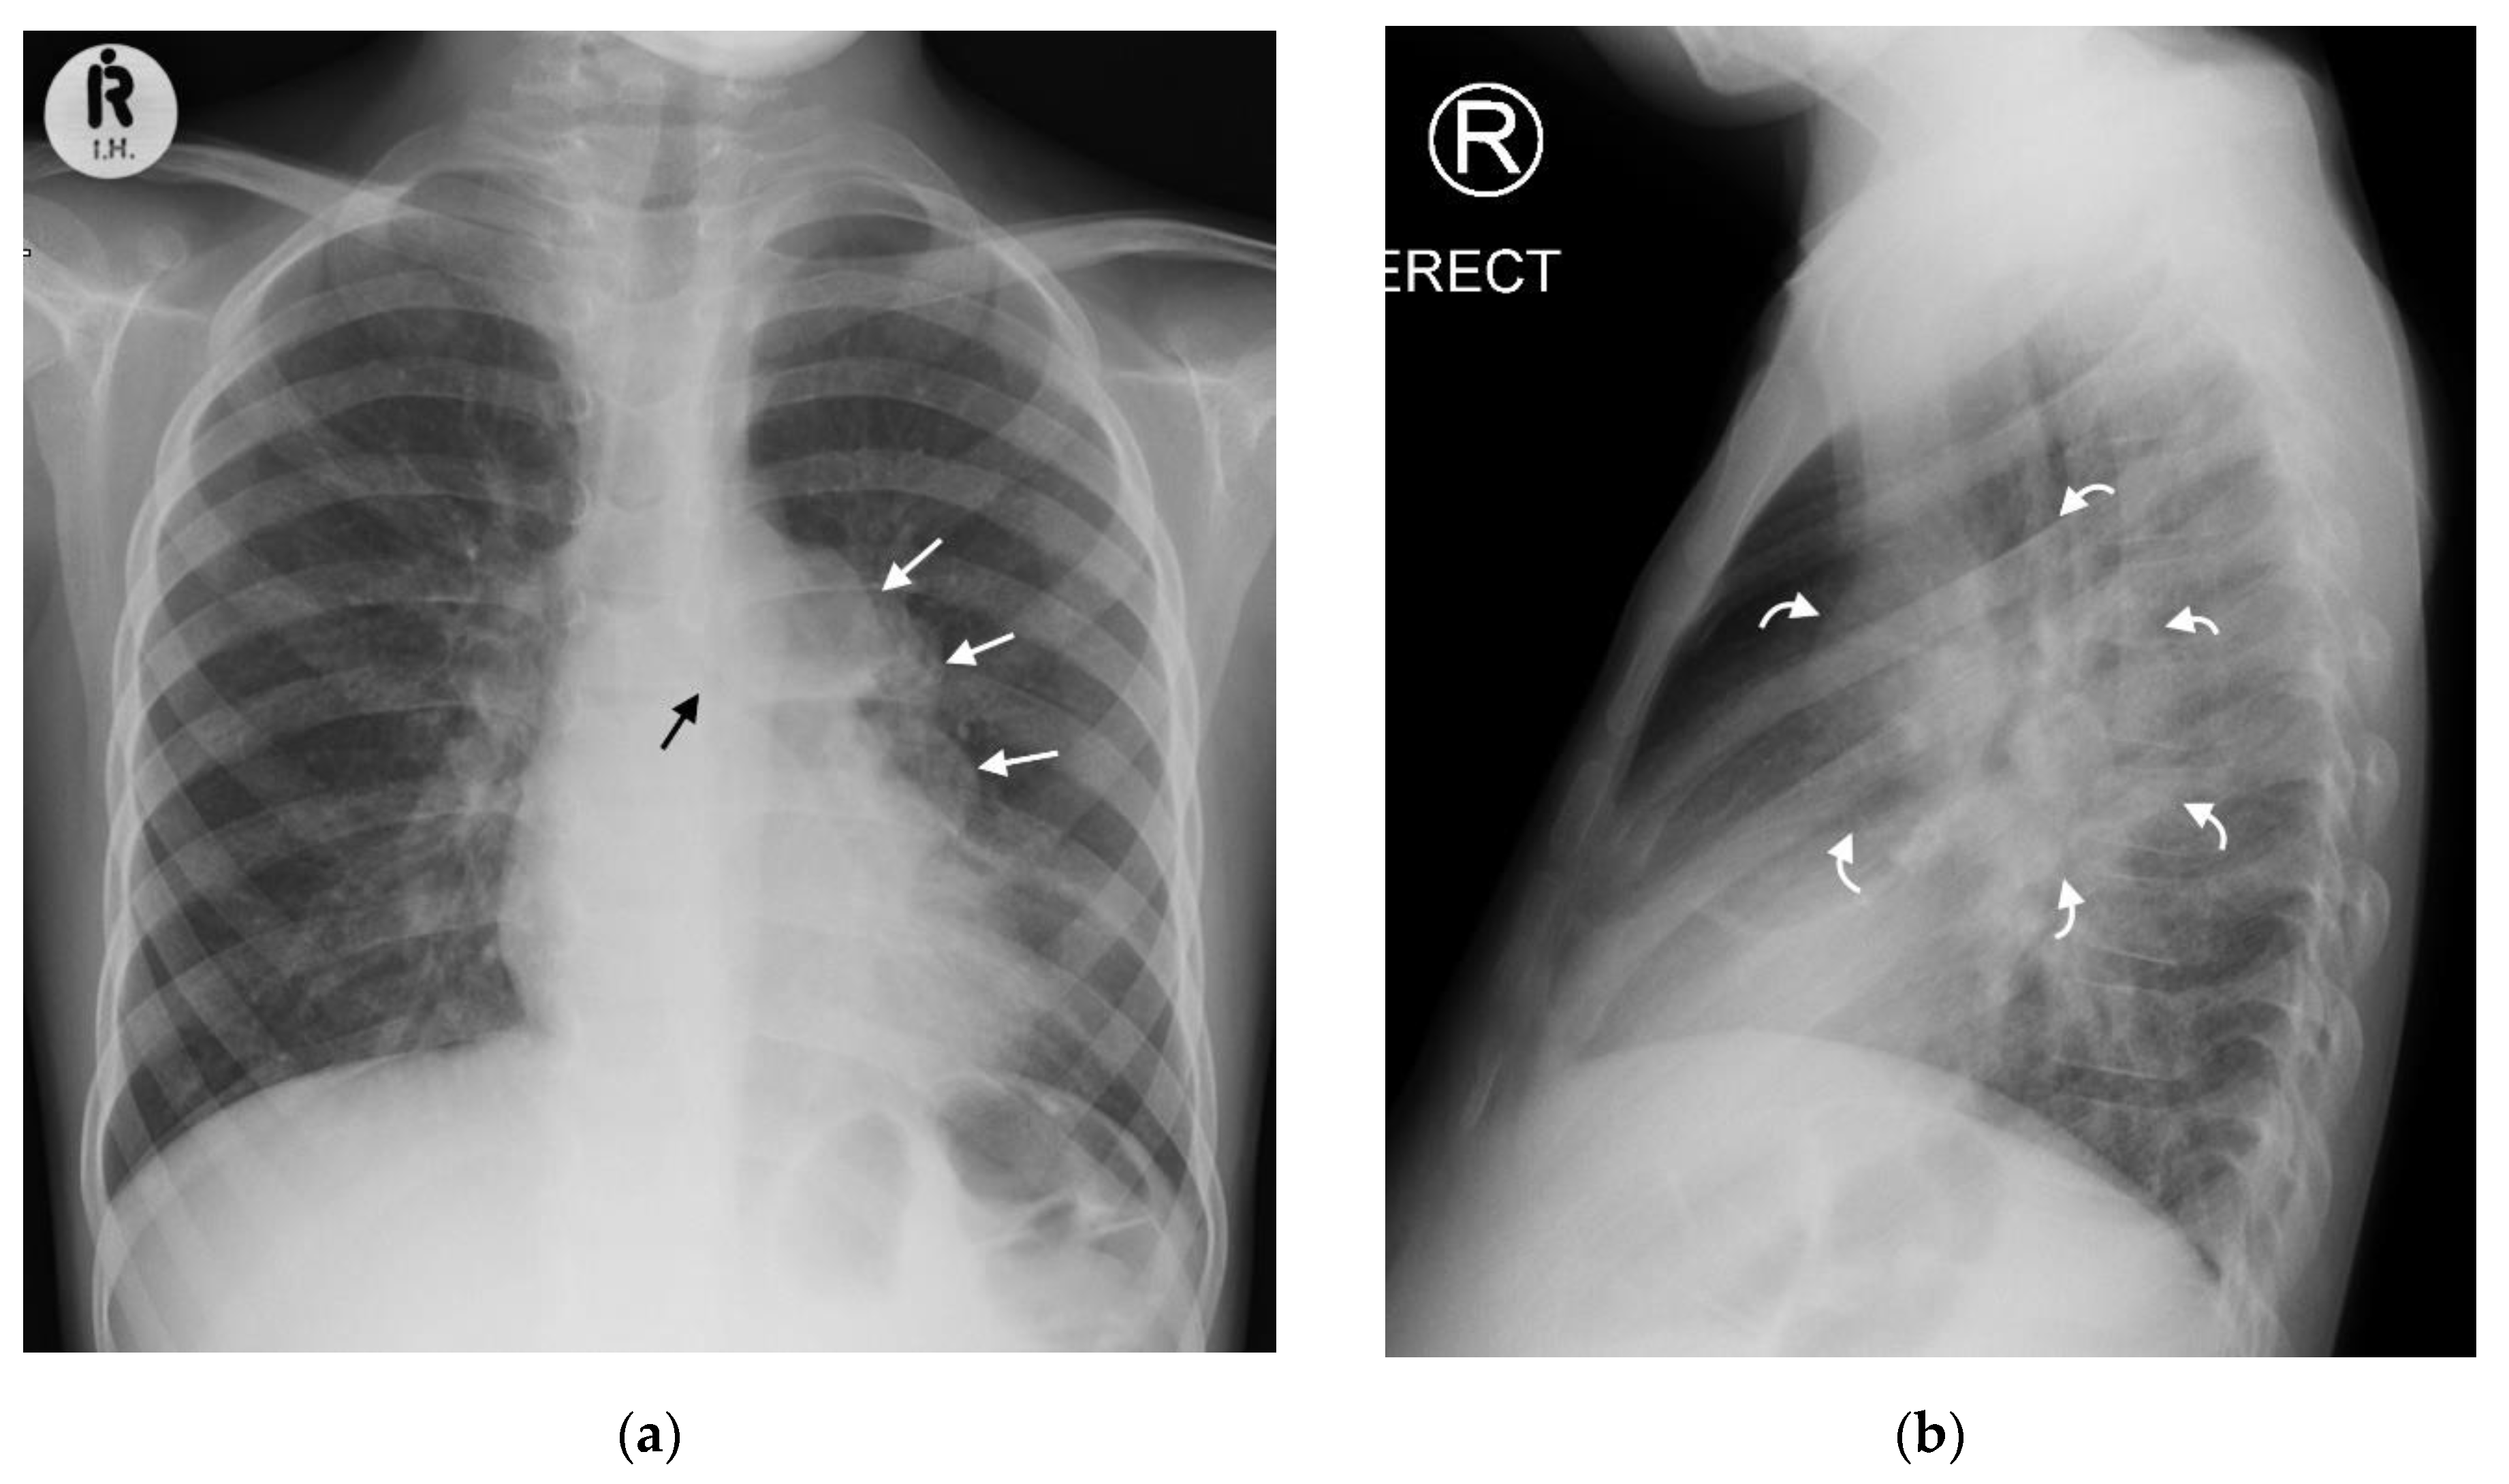

21 Year Old Male Patient With Fever And Hemoptysis Chest X Ray Interpretation